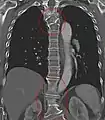

Several congenital block vertebrae in the transition from the thoracic to the lumbar spine and hemivertebrae.

Congenital block vertebra in the lumbar spine (partial vertebrae 3 and 4). The rear portion of the disc still exists.